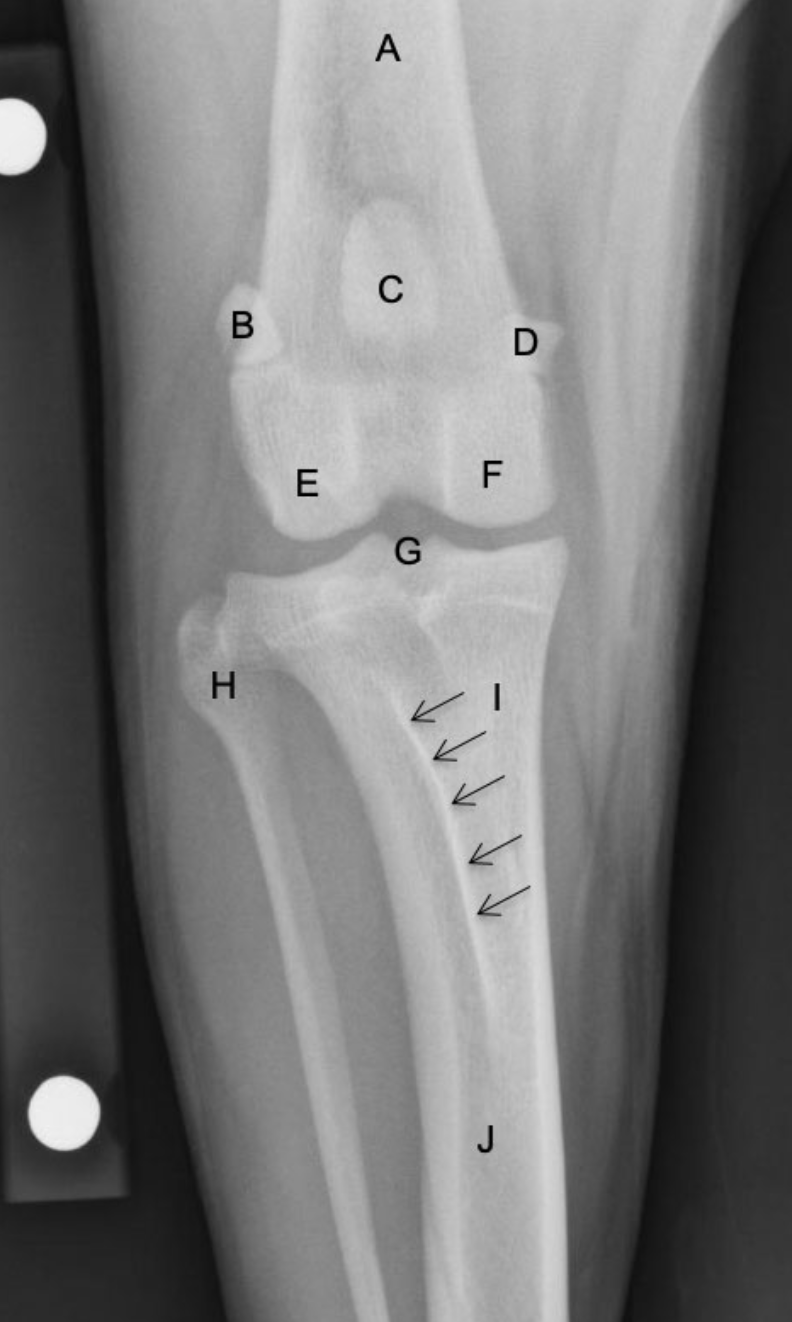

Label the structures

A

A = patella

B = distal femur

C = fabellae

D = tibia

E = fibula

How well did you know this?

1

Not at all

2

3

4

5

Perfectly